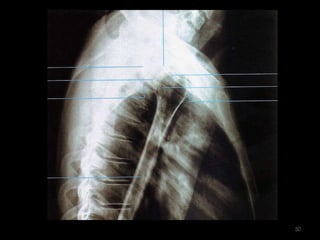

Incidência Lateral da Escápula 4

5